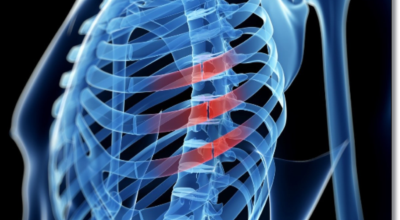

흉추와 복장뼈를 연결해서 가슴 전체를 둘러싸고 있는 가슴우리(흉강)을 형성하는 긴 곡선의 뼈를 말해요. 갈비뼈는 폐, 심장 등 내부 가슴 장기들을 지켜주고 가슴우리의 팽창과 수축으로 호흡을 도와주어요. 우리 몸은 총 12쌍의 갈비뼈를 갖고 있어요. 1~7번 갈비뼈는 복장뼈와 직접 관절로 연결되어 있어 참갈비뼈라고 하며, 8~12번 갈비뼈는 거짓 갈비뼈라고 하는데 거짓 갈비뼈 중 8, 9, 10번 갈비뼈는 하나의 연골을 통해 복장뼈와 연결되어 있고 나머지 11~12번째 갈비뼈는 뜬갈비뼈로 복장뼈와 연결되어 있지 않아요.

갈비뼈에 금이 가면 쿡쿡 찌르는 통증이 계속하여 느껴지는데요. 가만히 있어도 통증이 있으며 움직이면 훨씬 심해져요. 금이 간 정도에 따라 통증이 다르며 골절의 경우는 통증이 아주 심해져요.

허리 통증도 나타납니다. 갈비뼈에서 나타나는 통증은 흔하게 갈비뼈 부근을 넘어서 허리까지도 통증이 퍼지게 됩니다. 옆구리가 뜨끔하는 통증이 나타나기도 해요.